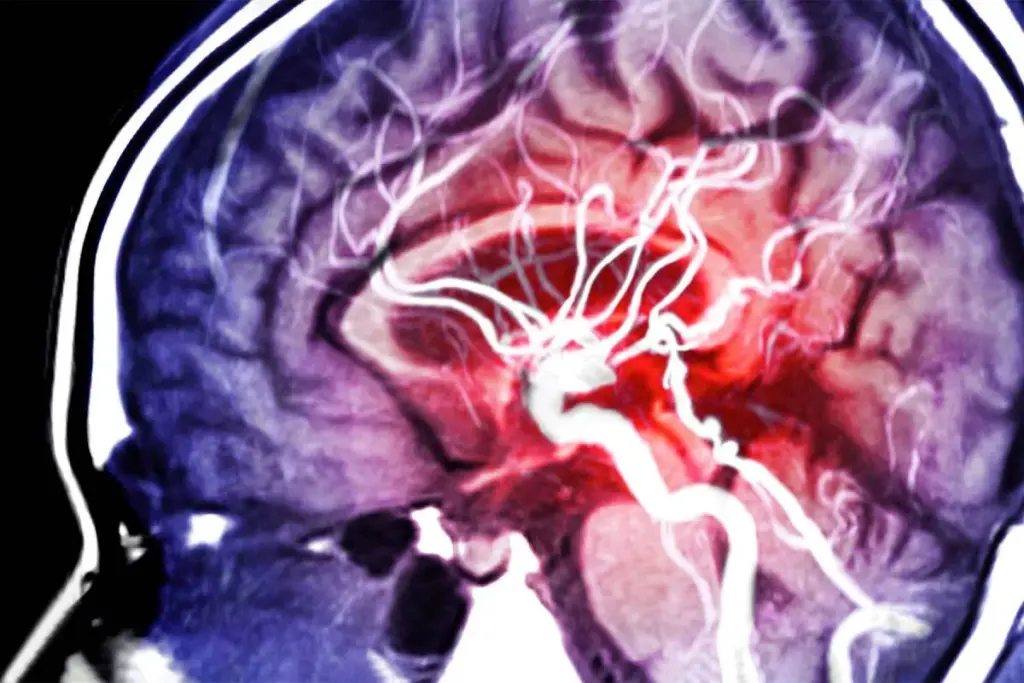

Imaging Techniques for Aortic Aneurysm Detection

Several methods are used to find aortic aneurysms. These include ultrasound, computed tomography (CT) scans, and magnetic resonance imaging (MRI). Ultrasound is often first because it’s non-invasive and doesn’t use radiation.

CT scans give detailed images and are great for checking aneurysm size and location. MRI is another good tool that uses no radiation and gives detailed images.